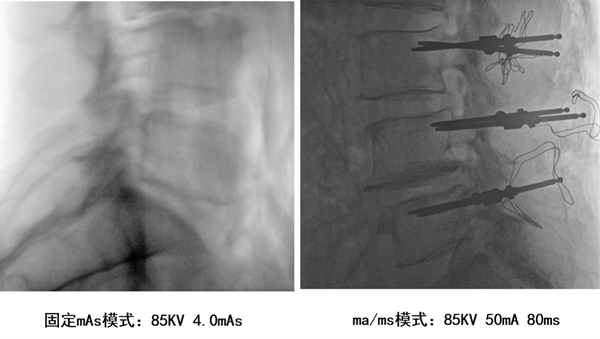

除了高清和大幅面成像,“悦画” 的低剂量辐射也是一大亮点。传统移动C臂通常mAs为固定模式,遇到体层较厚的患者时,必须要提升剂量才能获得较好的图像质量,所以传统移动C臂较难兼顾最佳图像与最低剂量的平衡。而“悦画”作为业内首款采用ma/ms自主曝光模式的移动C臂,它能够根据不同的手术部位自动调整曝光参数,从而达到“更好影像、更低剂量”的效果,既保障了手术所需的影像质量,又有效减少医生和患者的辐射剂量。